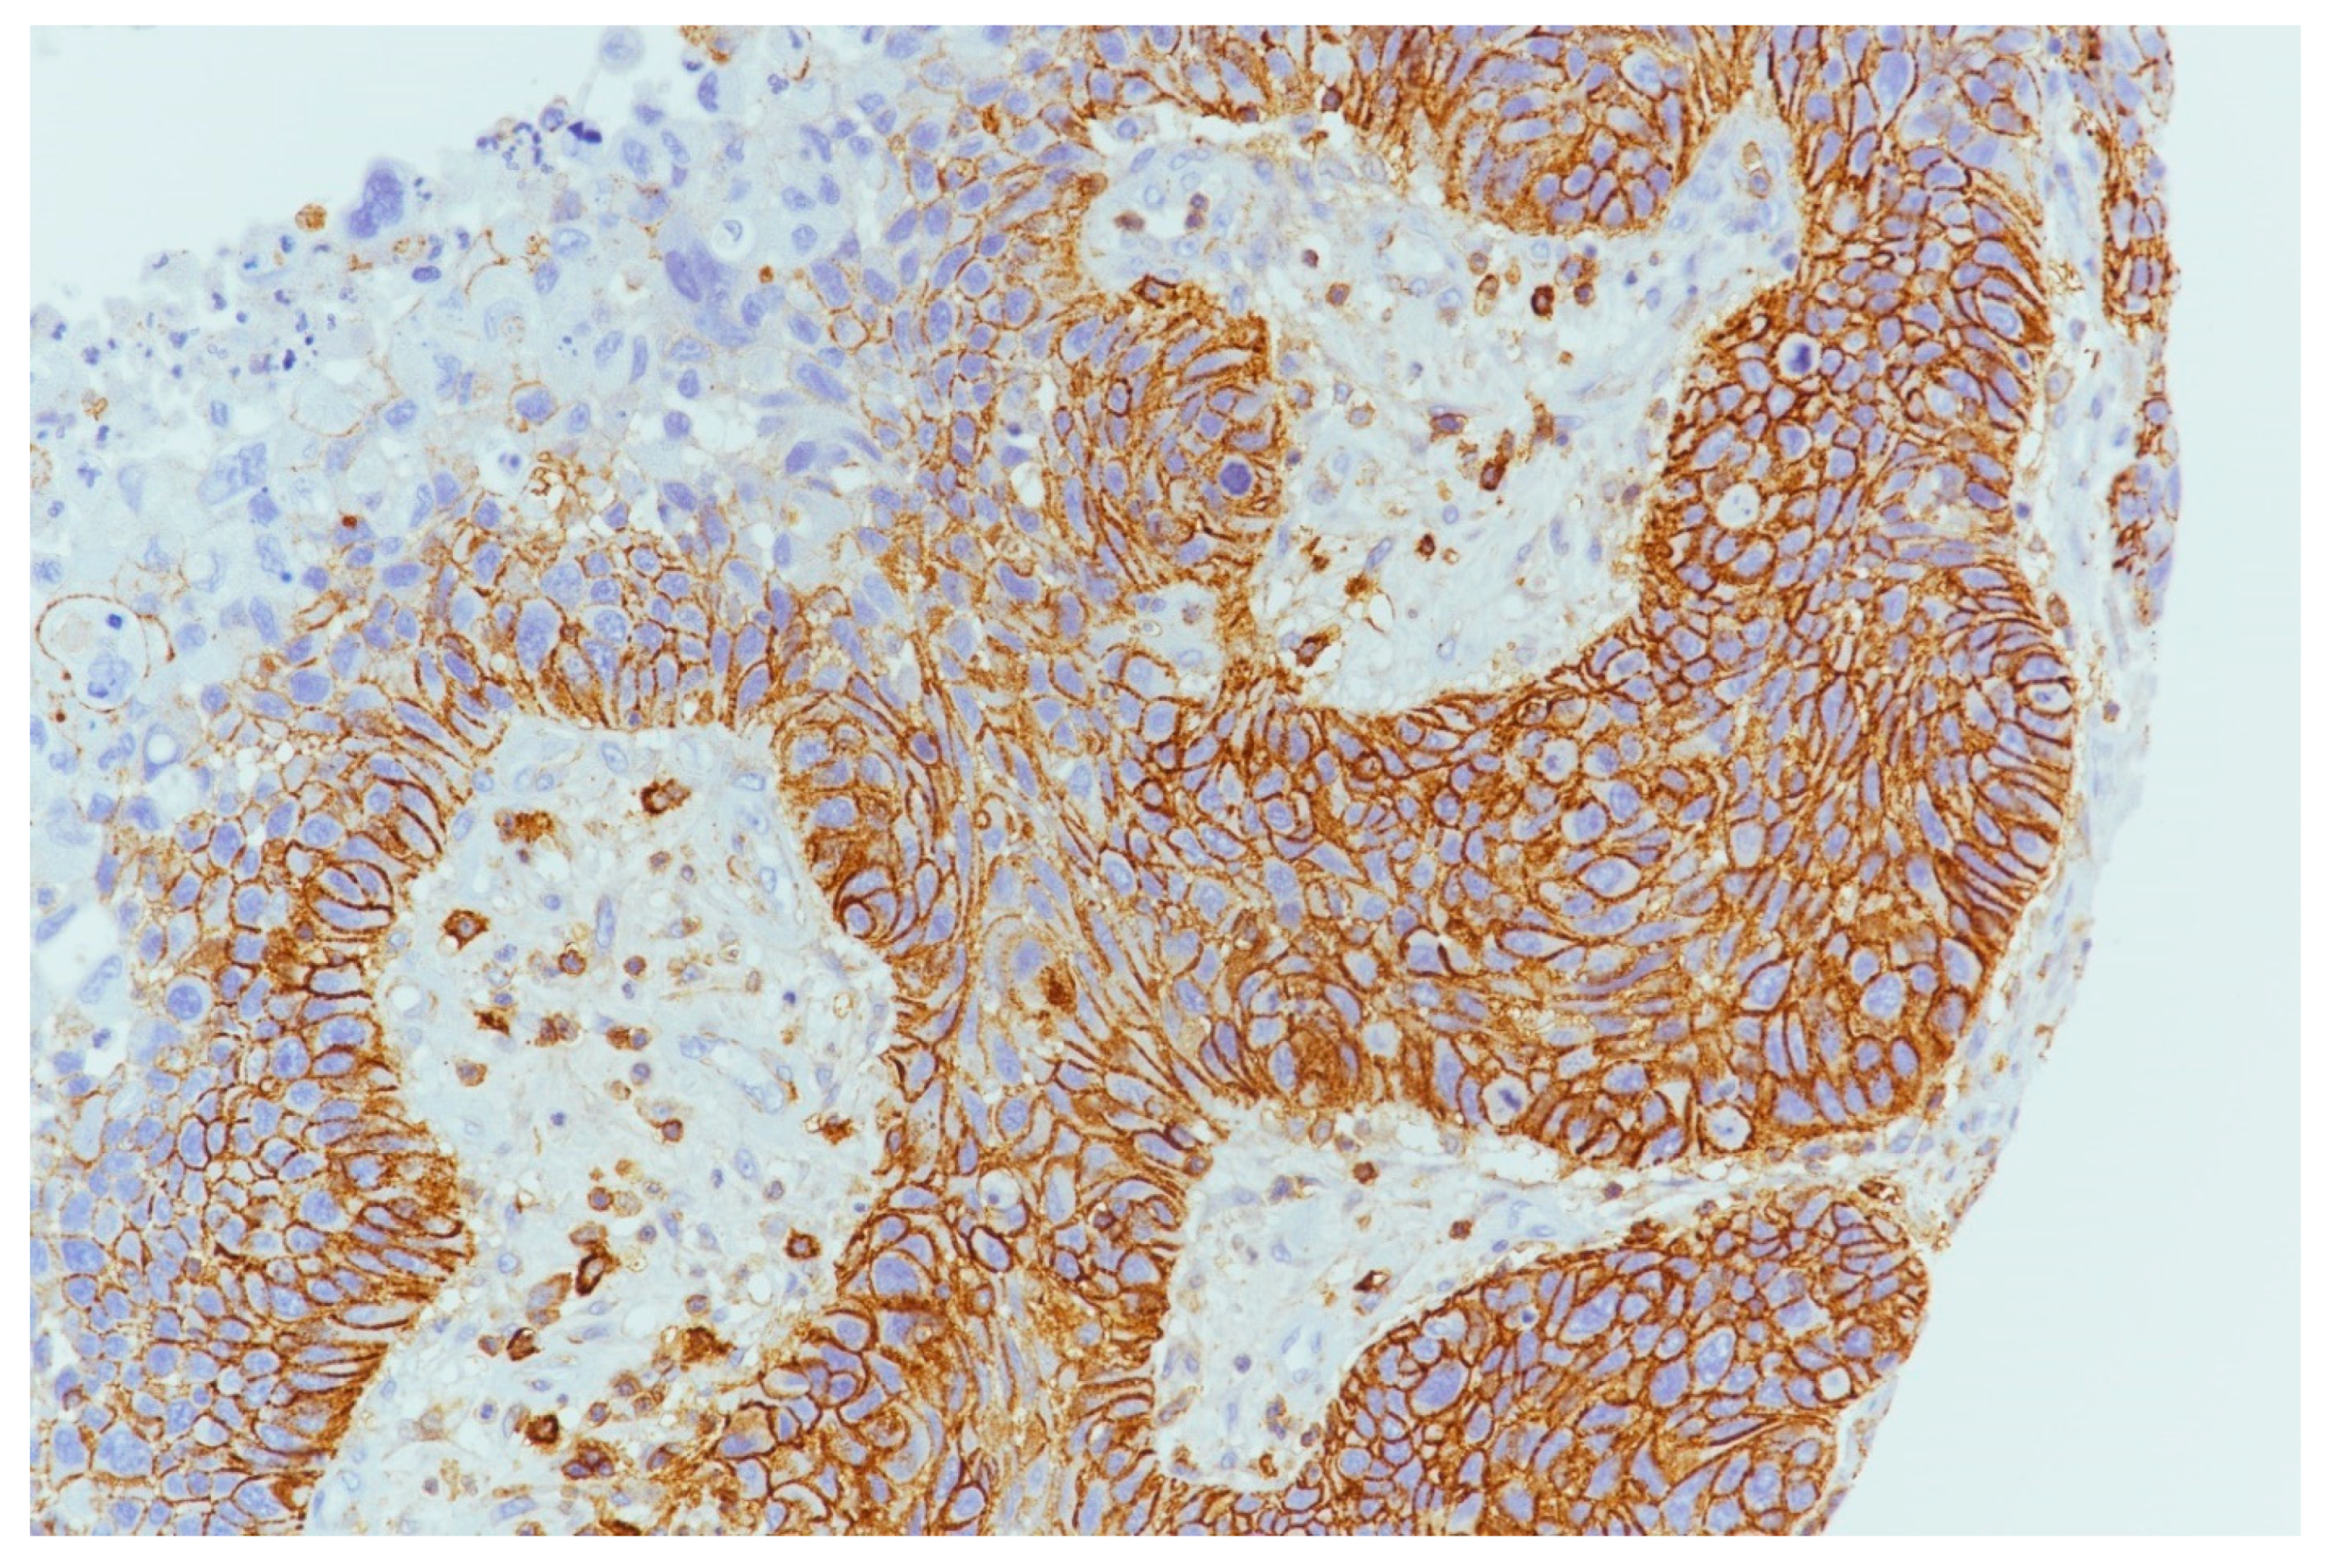

4.3. PDL1 Expression